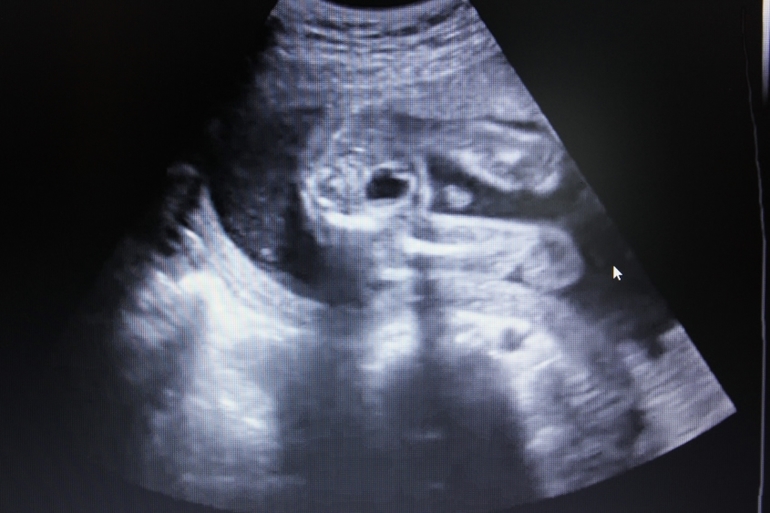

В начале мы его разбудили и он все время открывал ротик, зевал))

И вообще, хорошенький такой, у меня прям слезы текли)))))))